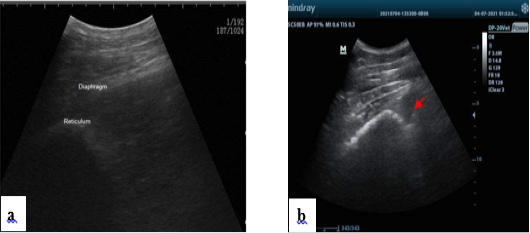

Figure 2

Normal ultrasonogram of the reticulum, notice half-moon shape (a). Presence of hypoechogenic fluid notice fibrin thread “arrow” in the reticular area in some diseased conditions (b).